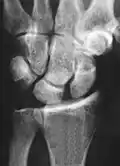

X-ray images indicate scapholunate ligament instability when the scapholunate distance is more than 3 mm, which is called scapholunate dissociation.[7] A static scapholunate instability is generally readily visible, but a dynamic scapholunate instability can only be seen radiographically in certain wrist positions or under certain loading conditions, such as when clenching the wrist, or loading the wrist in ulnar deviation.[6]

Dynamic instability: Increased scapholunate distance (between yellow lines) upon ulnar deviation of the wrist, but not otherwise. -